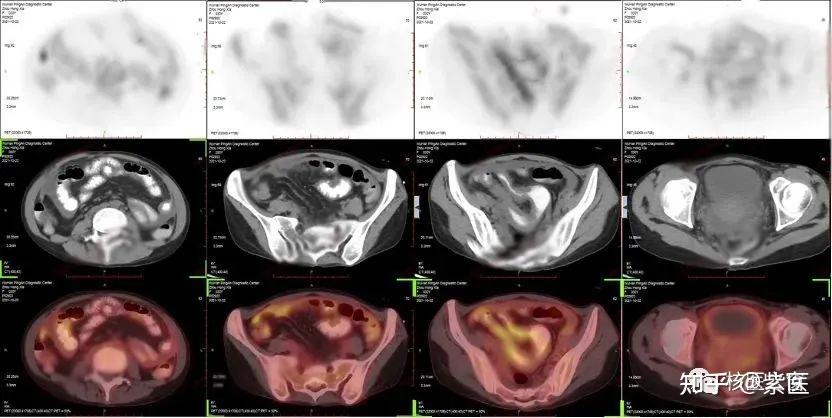

组成与原理PETCT结合了PET和CT两种技术PET能够显示人体内的功能代谢情况,而CT则能够提供精确的结构信息将这两种技术结合,可以对病灶进行定性和定位,提高诊断的准确性临床应用PETCT在临床中主要用于癌症的诊断,特别是用于鉴别良性和恶性肿瘤例如,当发现肺部有一个结节,而普通CT或增强CT不能。

什么是PETCT检查呢?PETCT检查和CT检查是不同的两种检查,两者之间会有不一样地方,不能一概而论也许有很多人对PETCT 检查的认识并不多,下面就来一起看看什么是PETCT检查以及PETCT和CT检查的区别 PETCT将两个相当成熟的技术融合在一起,实现了PET和CT图像的同机融合使PET的功能显像与螺旋CT的精细。